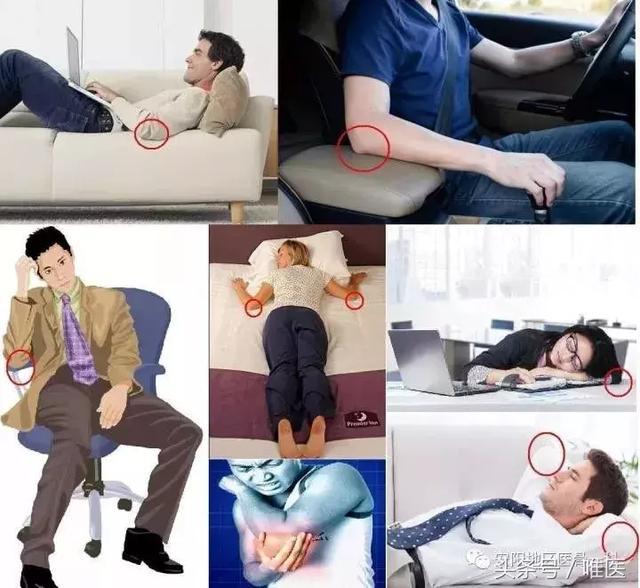

肘管綜合征是一種非常常見的勞損性疾病,主要和以肘部動作為主的職業和運動有關,同時還與很多情況有關,比如:睡覺時手臂搭在脖子後面,手肘彎曲;長期文案工作,打字、操作鍵盤時肘部受壓;長期用肘部支撐或肘部受壓著休息;“睡覺癱”等。